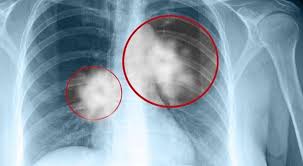

Küçük hücreli olmayan akciğer kanseri çok daha yaygındır ve genellikle küçük hücreli akciğer kanserinden daha yavaş büyür ve yayılır. Küçük hücreli akciğer kanseri, tüm akciğer kanserlerinin yaklaşık yüzde 15’ini oluşturur. Bu tip akciğer kanseri hızla büyür, tanı konulurken ilerleyip vücudun diğer bölgelerine hızla yayılabilir. Akciğer Kanseri Belirtileri Nelerdir? Akciğer kanseri belirtileri ve semptomları genellikle hastalık ilerleyince ortaya çıkar. Bununla birlikte, bazı insanlarda görülen erken belirtiler şunlardır: · İyileşmeyen öksürük, · Ses kısıklığı, · Balgam veya öksürme ile atılan kanlı balgam, · Güçsüzlük, · Hırıltı, · Tekrarlayan veya iyileşmeyen enfeksiyonlar, · Öksürük veya kahkaha ile kötüleşen göğüs ağrısı. İlerlemiş akciğer kanseri semptomları arasında öksürük, nefes darlığı, göğüs ağrısı, yorgunluk ve/veya istenmeyen kilo kaybı bulunur. Kanser başka yerlere yayılırsa ortaya çıkabilecek belirti ve semptomlar arasında kemik ağrısı, baş ağrısı, kas güçsüzlüğü ve/veya göz kapağı sarkması bulunurtr Akciğer Kanseri Nasıl Teşhis Edilir ve Yönetilir? Genellikle, bir hastanın akciğer kanseri olabileceği şüphesi, göğüs görüntülemede anormal bir bulgu olunca veya hastalık öksürük, nefes darlığı, göğüs ağrısı, yorgunluk ve/veya kilo kaybı gibi semptomlara neden olacak kadar ilerlediğinde oluşur. Tanı biyopsi veya şüpheli kitleden hücre veya dokuların çıkarılmasını gerektirir. Biyopsiler soluk borusundan (bronkoskopi olarak adlandırılır) bir kamerayla veya deri yoluyla akciğer tümörüne sokulan bir iğneden yapılabilir. Bu yaklaşımlar başarılı olmazsa, yeterli tanı için ameliyat gerekebilir. Biyopsi, kanser olup olmadığını ve hangi tip akciğer kanseri olduğunu belirlemede önemlidir. Akciğer kanseri taraması Akciğer kanseri taraması, hastalığı erken evrede yakalayabilmek için kanser belirtisi olmayan akciğer kanseri geliştirme riski yüksek olan sağlıklı bir bireylere düşük doz göğüs BT görüntülemesi yapılmasını kapsar. Bu taramanın, yüksek kalitede yapıldığında kabul edilebilir oranda akciğer kanserinden ölen insan sayısını azalttığı bulunmuştur.Not:Doktorunuza danışın.